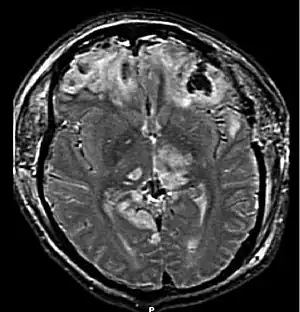

| CT scan showing cerebral contusions, hemorrhage within the hemispheres, subdural hematoma on the left, and skull fractures[1] | |